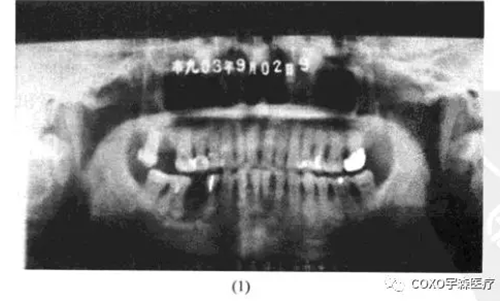

x線片示:雙側(cè)后牙區(qū)高密度陰影(圖13-7),初步診斷:雙側(cè)后牙區(qū)根尖周骨質(zhì)結(jié)構(gòu)異常,伴感染,收入院。